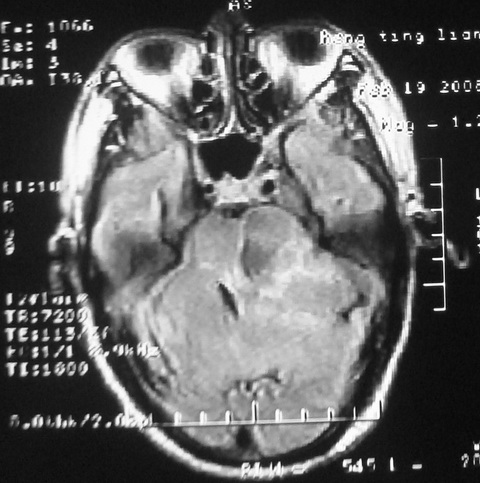

m,72,头疼,头晕两年,伴视力模糊三月,饮食呛咳两天。pe:颈部抵抗,左眼突出,左眼瞳孔约3mm,对光反射消失,双眼失明,伸舌困难,双肺呼吸音粗,心率110次/分,左上肢肌力i级,左下肢屈曲,肌张力高。现有08年2月19mri平扫及10年2月8日mri增强请会诊。ct病灶呈低密度伴散在点、片状等密度区,无明确钙化(无ct片资料可供上传)。[

脑外肿瘤,表皮样囊肿可能性大。

考虑表皮样囊肿。

脑外肿瘤,病灶呈匍匐蔓延,表皮样囊肿可能性大。

脑外肿瘤,病灶呈匍匐蔓延,表皮样囊肿可能性大。支持!